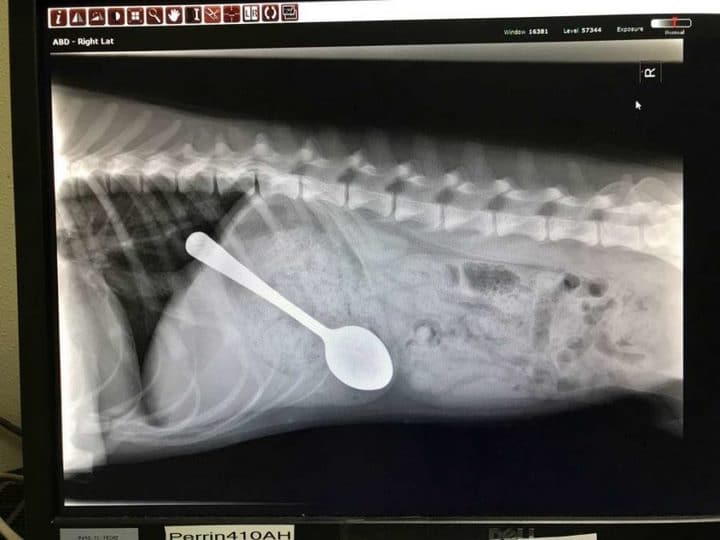

Los veterinarios vieron la cuchara en el interior del perro gracias a una radiografía. Actuaron rápido: pusieron anestesia al animal y sacaron el cubierto de su estómago. Según parece, era la primera vez que veían algo así...